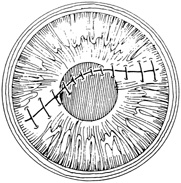

A number of options are available for suturing a corneal laceration. Tissue margins should appose as precisely as possible while suturing. The simplest method is to progressively halve the wound with simple interrupted sutures. Corneal sutures should be approximately 90% to 95% depth through the stroma, 1.5 mm in length, and of equal depth on each side of the wound. Shallow sutures create internal wound gape, whereas sutures of unequal length and depth on each side of the wound result in wound override. Sutures should generally not be passed through 100% thickness because the tract may theoretically act as a conduit allowing microorganisms from the external surface to enter the eye. For shelved lacerations, sutures should be placed equidistant with respect to the internal aspect of the wound and tied with minimal tension to achieve good tissue apposition, avoiding wound slippage with consequent tissue override (Fig. 5). Wounds with edematous or irregular margins generally require longer sutures for closure.

Placement of sutures through the visual axis should be avoided. If it is necessary to pass sutures near the visual axis, they may be placed on each side of, but not directly through, the axis itself. In addition, the bite closest to the visual axis may be made shorter, thus avoiding this area (Fig. 6). A “no-touch” technique also may be used to minimize trauma at the visual axis. With this technique, the eye is secured by grasping the globe with forceps away from the cornea. The suture needle end is then placed perpendicular to the corneal surface, and the needle is rotated through the corneal tissue following the needle's curvature (Fig. 7).8